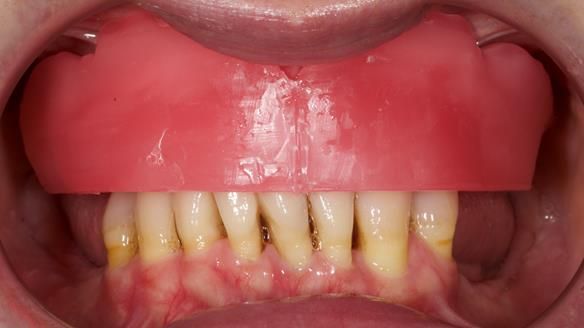

She had previously suffered from generalised periodontitis – stage IV, grade C, currently stable, with reduced attachment across the upper arch.

By the time she came to me, her periodontal condition was stable — but the aesthetics in the upper jaw were very poor.

Dr Syed Abad — my colleague and a Specialist in Periodontics — had successfully stabilised her gum health.

We provided her with an immediate upper denture (Mk 1), followed by a definitive metal-based upper denture (Mk 2). A lower removable partial denture was discussed, to be made only if needed once the upper treatment was complete. However, at review, this wasn’t necessary — Adnana had excellent neuromuscular control and function, even with a shortened dental arch (SDA).

- Immediate denture (Mk 1) fitted the same day the teeth came out